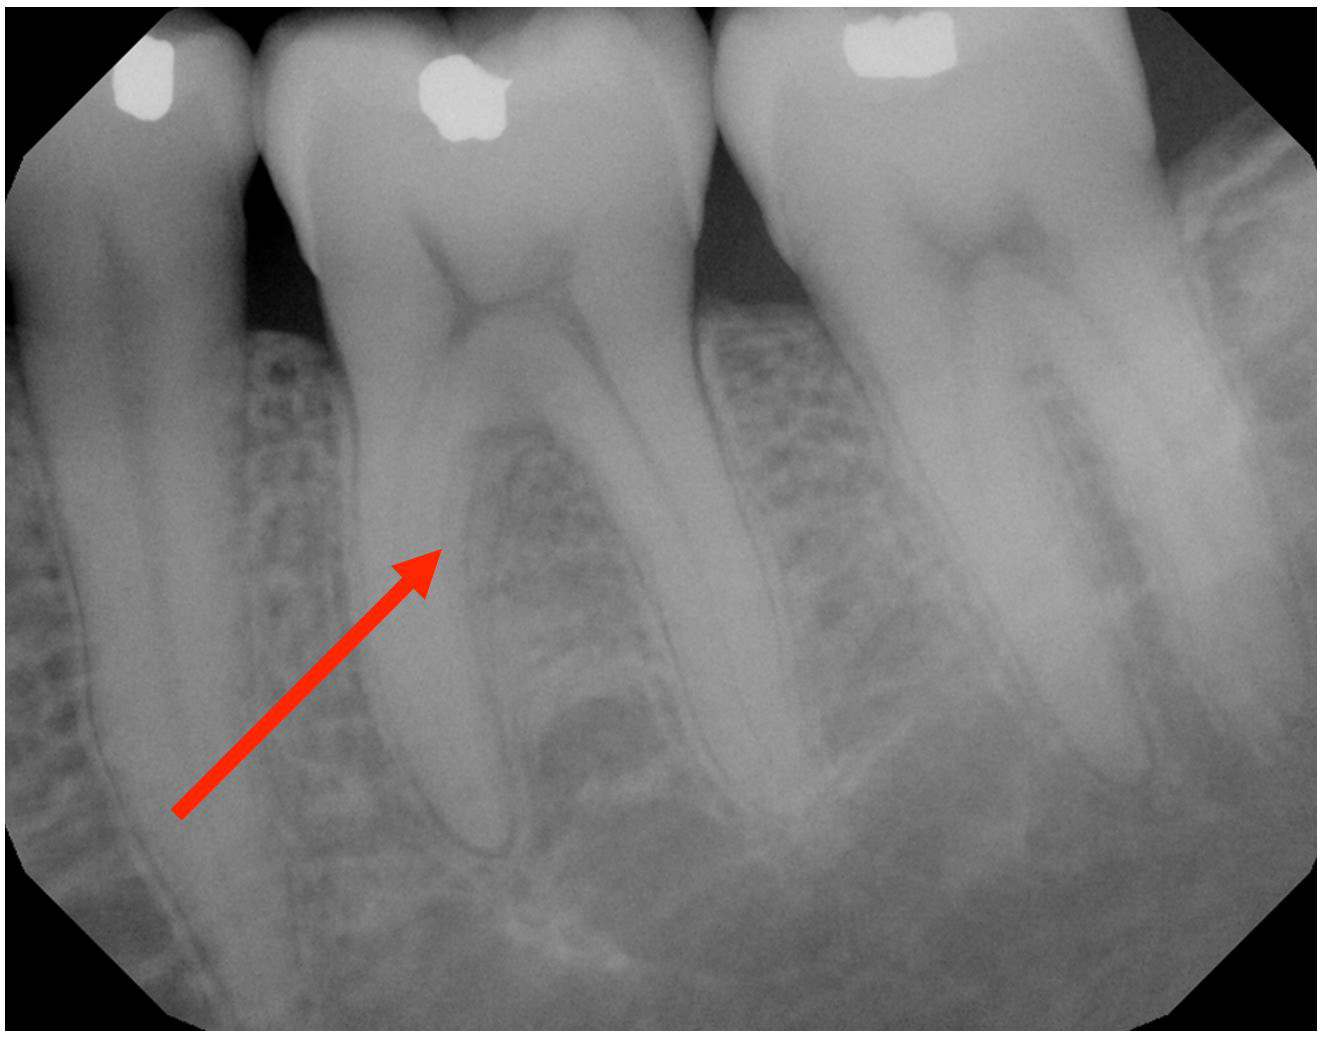

Laser Periodontal Treatment

*Follow-up x-rays 9-12 months after treatment